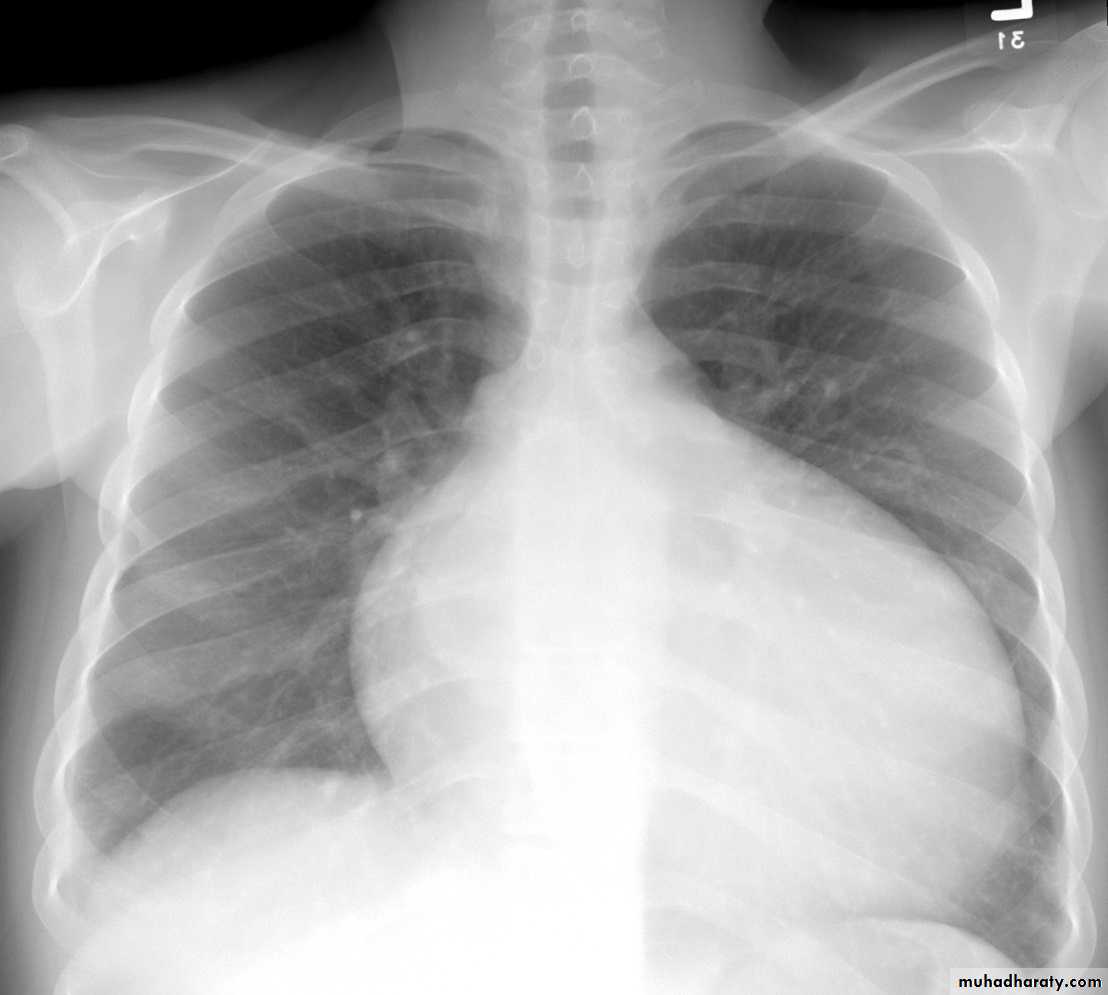

The heart is enlarged by dilation and hypertrophy of all chambers. The dilation and poor contractile function cause stasis of blood in cardiac chambers and predispose to development of fragile mural thrombi and emboli.

Manifested as right atrial and ventricular dilation, right ventricular hypertrophy and dilation of pulmonary artery, pulmonary hypertension developed.Ventricular septal defect:-

VSDs are the most common congenital heart defects and this like ASDs occur in isolation or in association with other cardiac malformations, the size and location of defect is variable ranging from minute to large defect and this may close spontaneously during infancy or childhood.Morphology:- In large defect associated with significant left to right shunt so right ventricle is hypertrophied and dilated, with pulmonary hypertension developed if this occur so reverse of shunt and cyanosis occur.

The oxygenated blood flows from the left ventricle to the lungs and is returned to the left atrium, so form volume overload to cause dilation and hypertrophy of left atrium and ventricle.

The proximal pulmonary arteries are also dilated with development of pulmonary hypertension and cause right ventricular hypertrophy and dilation and right atrial dilation.